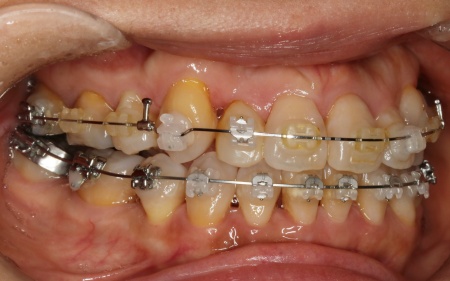

治療中

ワイヤー矯正を進めていくなかで、右上の前歯2本(中切歯、側切歯)が骨の中で根がくっついている癒合歯(ゆごうし)であることが判明しました。

この影響で、側切歯の位置がずれたまま中切歯と一緒に動いてしまい、単独での正確な位置調整が難しい状態です。

そのため患者様と相談し、側切歯の表側に歯科用プラスチックを盛って見た目を整え、噛み合わせに支障が出ないよう慎重に調整を行う措置をとりました。

また歯を効率よく動かすため、顎の骨に矯正用の小さなネジであるインプラントアンカーを埋め込み、それを固定源とすることでしっかりと歯を動かしながら、歯列と噛み合わせのバランスを整えています。